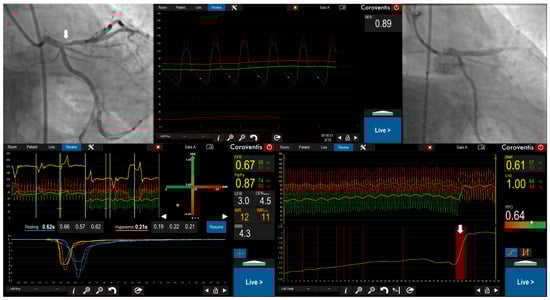

The Pullback Pressure Gradient: Transforming Invasive Coronary Physiology from Lesion Assessment to Disease Pattern Characterization—A Perspective

This perspective comprehensively analyzes the invasive pullback pressure gradient (PPG), a novel physiological index that characterizes the longitudinal distribution of coronary artery disease and guides revascularization strategy modified in 14% of patients in the PPG Global Registry based on PPG assessment. We trace

This perspective comprehensively analyzes the invasive pullback pressure gradient (PPG), a novel physiological index that characterizes the longitudinal distribution of coronary artery disease and guides revascularization strategy modified in 14% of patients in the PPG Global Registry based on PPG assessment. We trace the historical development from subjective pullback curve analysis to a standardized, quantitative metric and describe the procedural aspects of both motorized and manual PPG acquisition. We synthesize evidence supporting PPG’s clinical utility in predicting post-percutaneous coronary intervention outcomes, guiding revascularization decisions, and improving patient-centered outcomes. A central focus is PPG’s mechanistic role in explaining the physiological basis of discordance between fractional flow reserve (FFR) and instantaneous wave-free ratio (iFR), linking focal disease to FFR-positive/iFR-negative patterns and diffuse disease to FFR-negative/iFR-positive patterns. We conclude that PPG represents a fundamental advancement in coronary physiology, shifting clinical focus from individual stenoses to overall disease patterns. This paradigm shift provides deeper understanding of coronary artery disease pathophysiology and offers a powerful predictive tool to guide personalized revascularization strategies. Prospective randomized trials will be essential to solidify its role as a cornerstone of modern interventional cardiology practice.